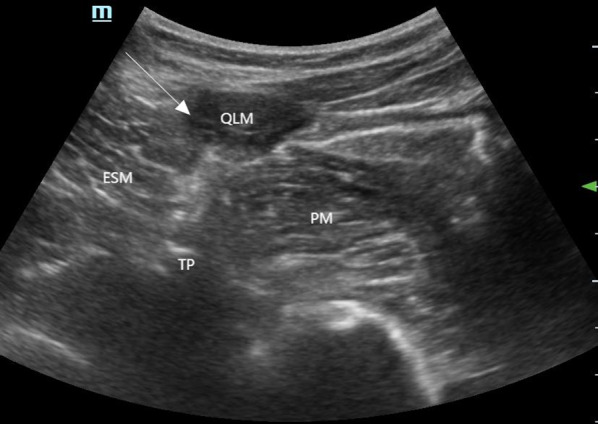

Introduction: Breast cancer surgery is a common surgical procedure often associated with acute and chronic postoperative pain. As part of multimodal analgesia, the erector spinae plane block (ESPB) has been shown to effectively alleviate pain after breast cancer surgery. This study is the first to apply the posterior quadratus lumborum block (posterior QLB) for perioperative analgesia in breast cancer surgery. The aim of this research was to evaluate whether ESPB and QLB2 can relieve acute and chronic pain following breast cancer surgery.

Methods: A total of 120 female patients undergoing breast cancer surgery were randomly assigned to receive either ESPB, posterior QLB, or no intervention. All patients were administered sufentanil patient-controlled intravenous analgesia postoperatively. The primary outcome was the visual analog scale (VAS) pain scores recorded at 2, 6, 18, 24, and 48 h post-surgery under rest and motion conditions. Secondary outcomes included the incidence of moderate-to-severe pain within 24 and 48 h post-surgery, intraoperative fentanyl cumulative dosage, postoperative rescue analgesia, chronic pain incidence, recovery quality of life, and adverse events.

Conclusion: Compared with conventional intravenous analgesia, the combination of ultrasound-guided ESPB and posterior QLB significantly reduces the incidence of moderate-to-severe pain and the need for rescue analgesia within 24 h post-surgery. Furthermore, a single posterior QLB significantly reduces the incidence of chronic pain at 3 months post-surgery in patients with breast cancer.